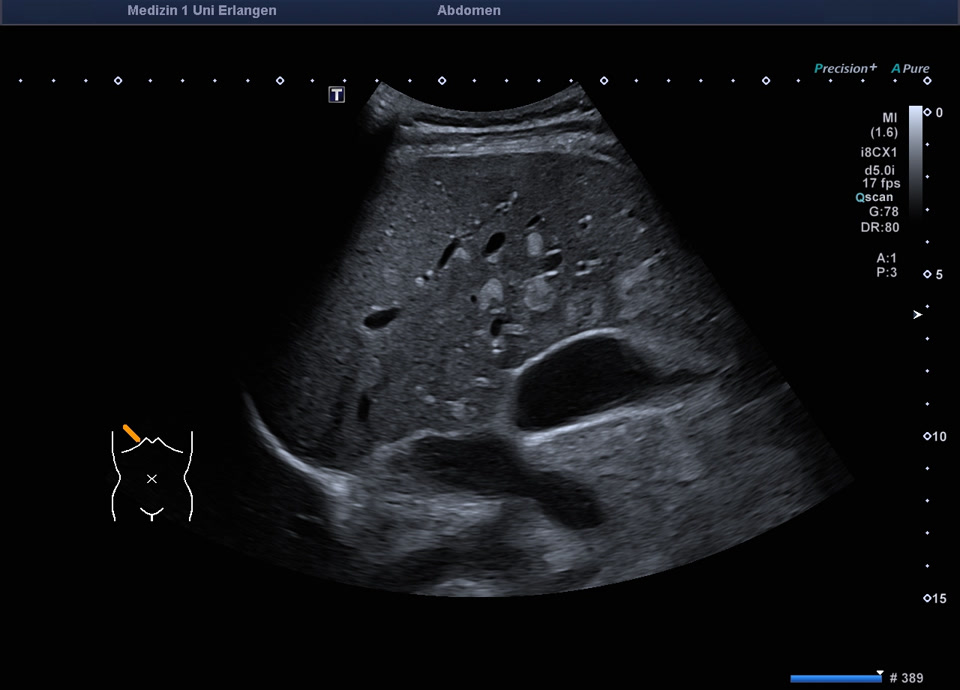

Fokale Mehrverfettung

Lobuläre Mehrverfettung des rechten Leberlappens (siehe auch nächstes Bild)